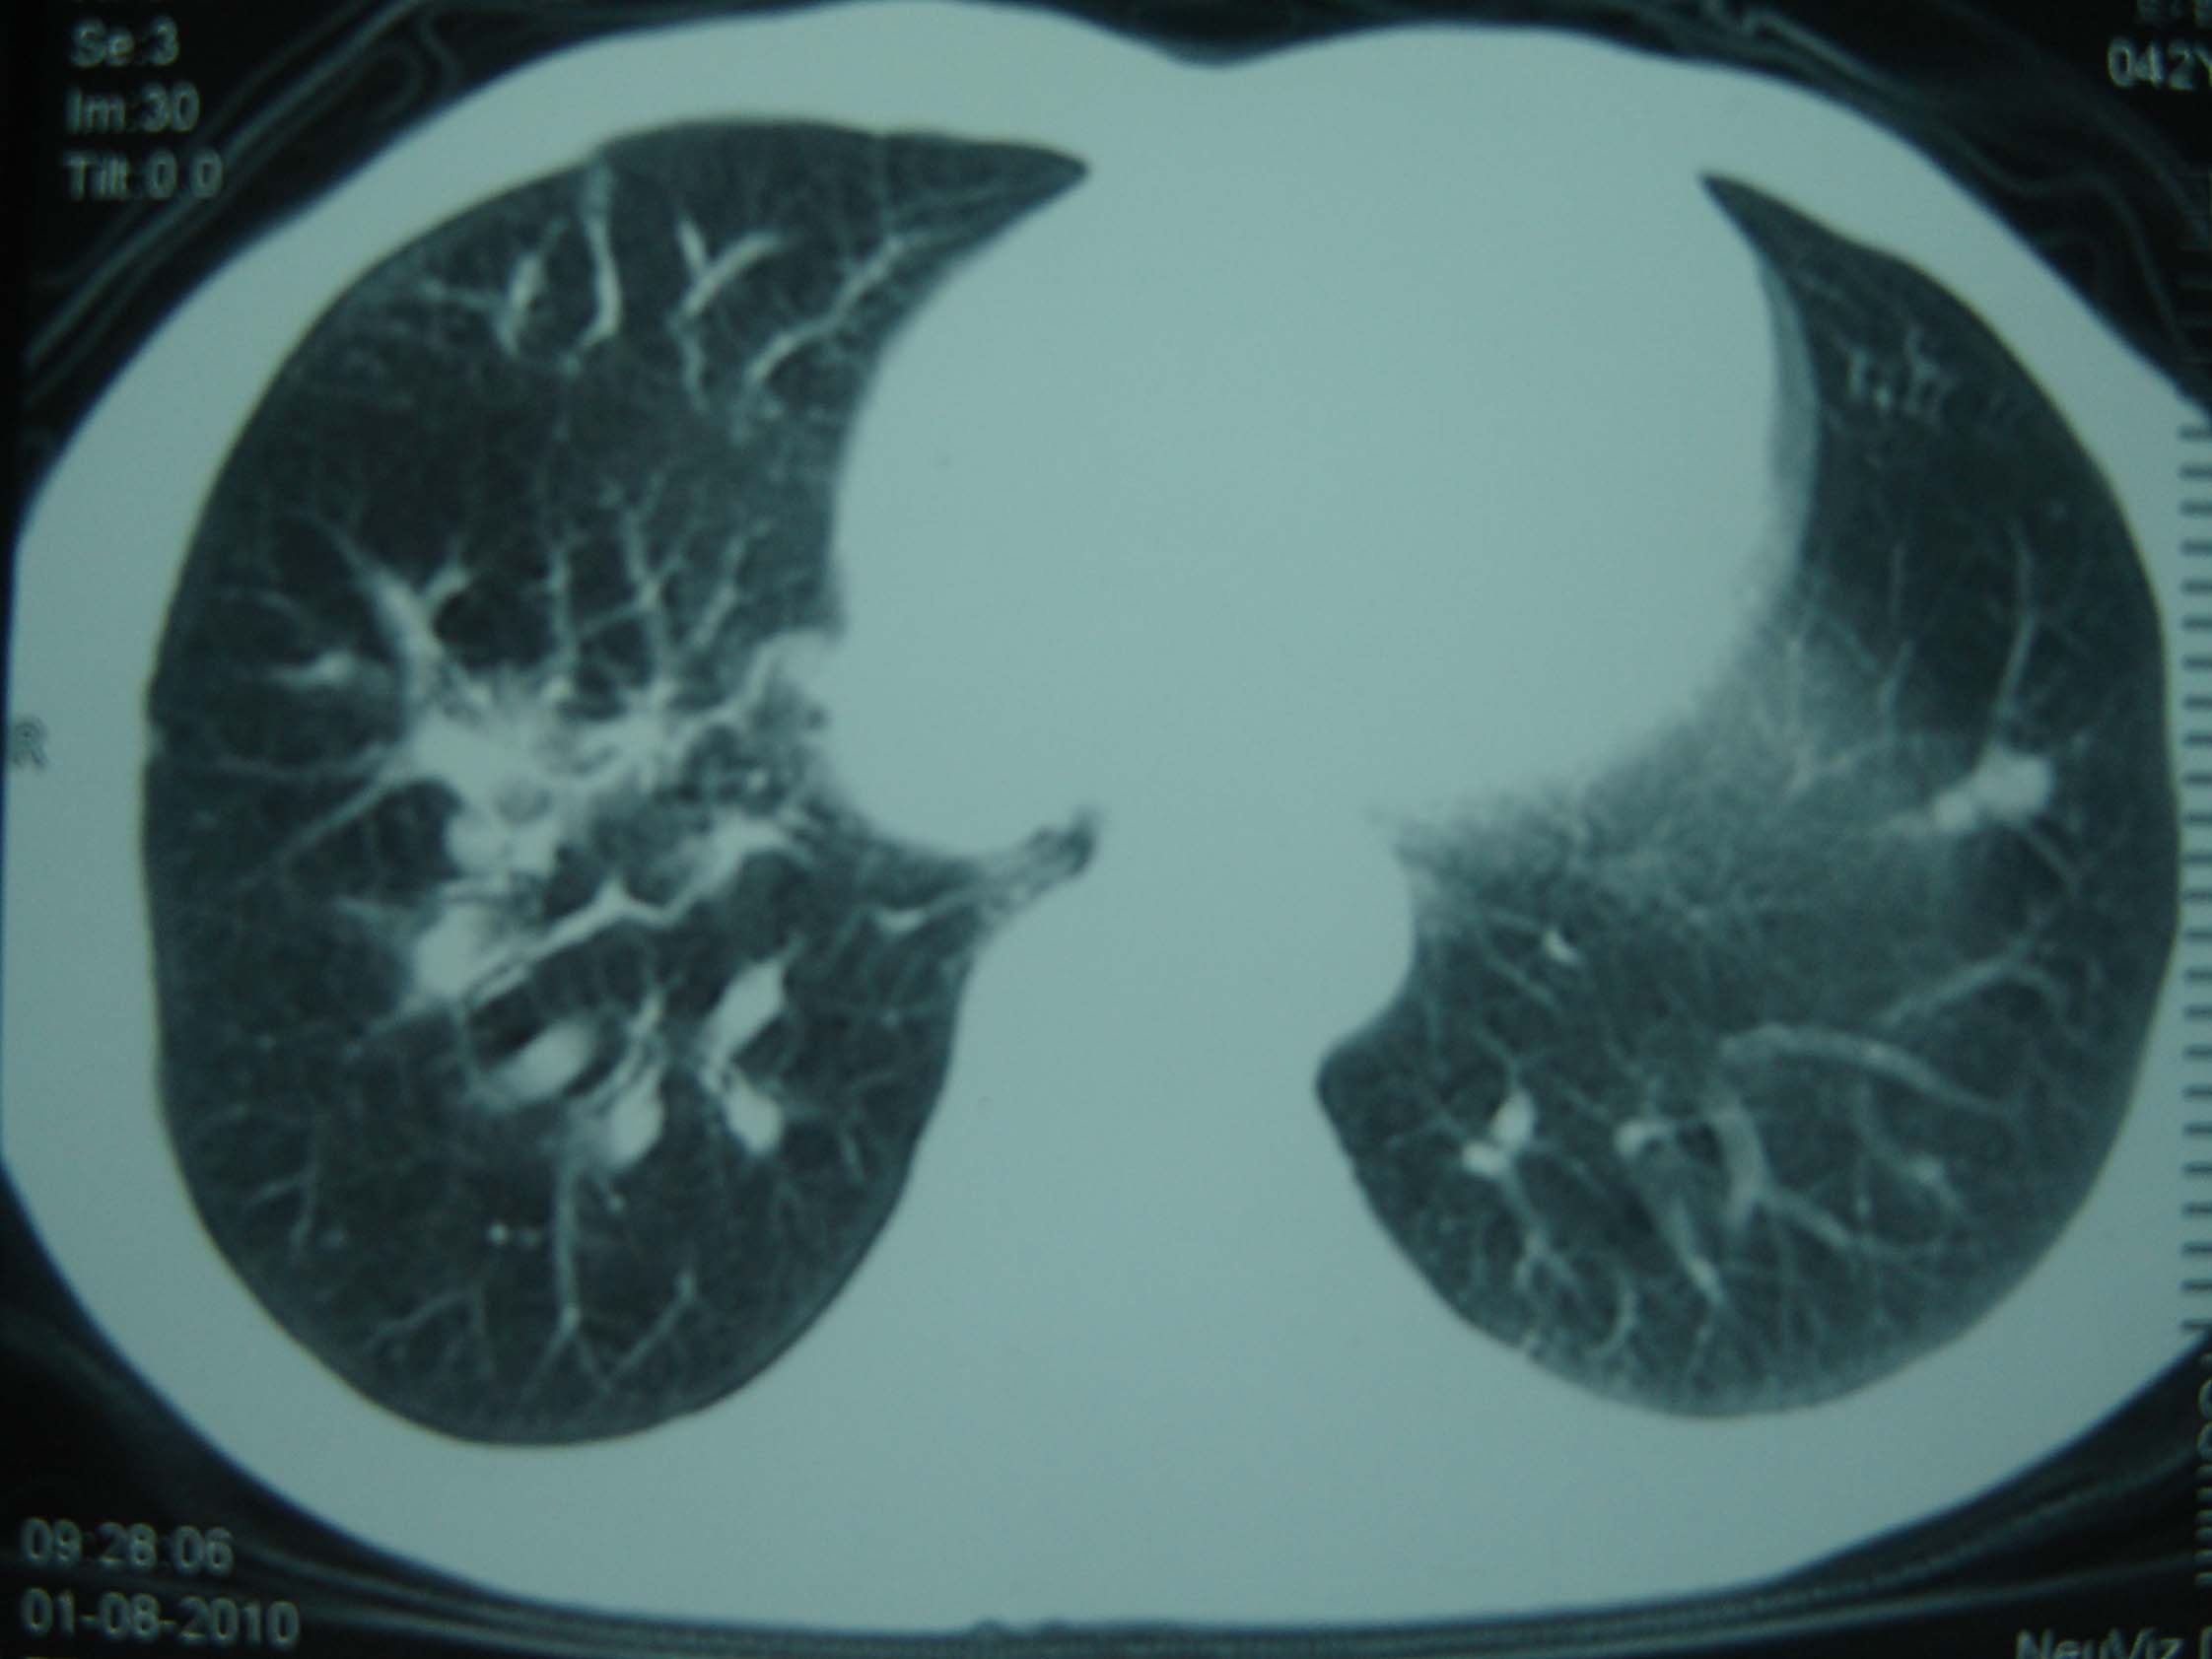

标题: CT25321:两肺多发结节 请会诊 [打印本页]

标题: CT25321:两肺多发结节 请会诊

男 、43岁,咳嗽胸痛,装修工,平时接触粉尘较多,有吸烟史10多年,纤维支气管镜检查未发现异常,胃镜、腹部b超检查亦未发现异常,颈部淋巴结活检未发现肿瘤细胞。

不能排除转移,如果不能找到原发灶,只有短期随访。

结节病?转移瘤?

1)考虑双肺及胸膜多发性转移瘤。2)肺气肿。